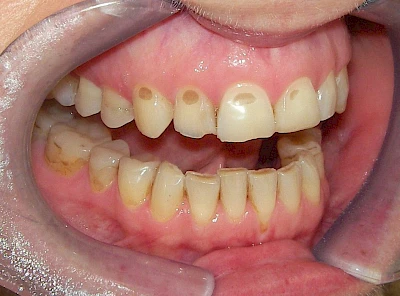

Gerade bei Kindern und Jugendlichen werden zunehmend häufiger bräunliche Verfärbungen mitunter auch mit Formveränderungen (die Oberfläche ist rauh oder zerklüftet) der Zähne beobachtet. Meist sind Schneidezähne oder Backenzähne betroffen. Dies könnte ein Hinweis auf sogenannte Kreidezähne (MIH: Molaren-Inzisiven-Hypomineralisation) sein.

Bräunliche Verfärbung

- Durch übermäßige Fluorideinlagerung in der Zahnreifung (mehrere Zähne, weißlich-fleckig)